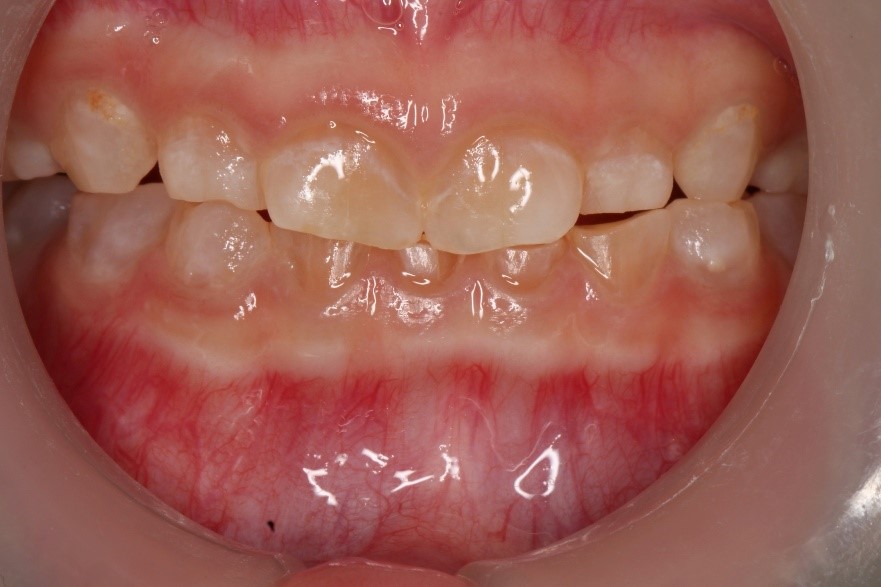

Anterior view of the dentition before treatment

Dentinogenesis imperfecta-Type I (DGI-Type I) is a dental developmental anomaly observed in some osteogenesis imperfecta (OI) patients. Teeth in this dental anomaly often appear discoloured, and their enamel breaks easily due to the defective underlying dentine. The affected teeth are abraded rapidly if the condition is not identified early. Early diagnosis allows the proper execution of age-based preventive and rehabilitation strategies. Protection of the affected teeth enables various functions of the dentition, such as mastication and dental aesthetics, which could be maintained effectively in growing OI children. Thus ensuring the oral health-related quality of life of the patients with OI is at par with that of their healthy counterparts.